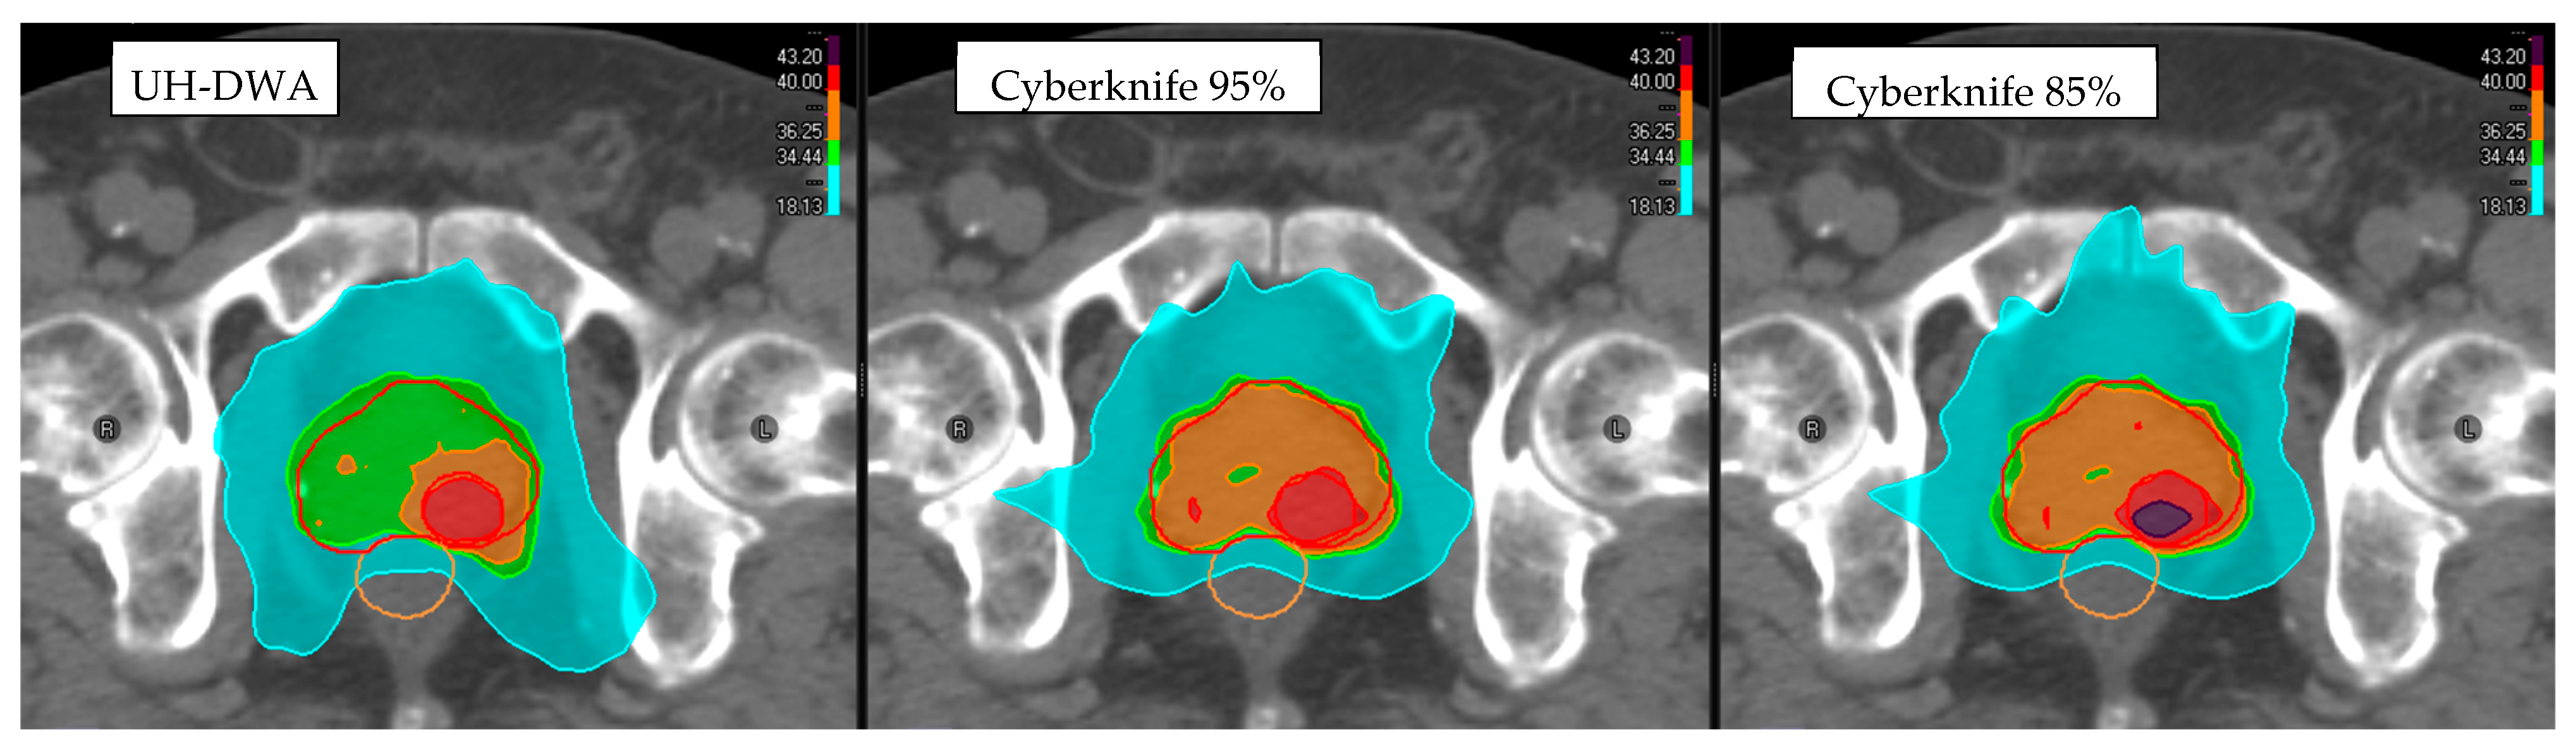

3. Results

3.1. Target Coverage